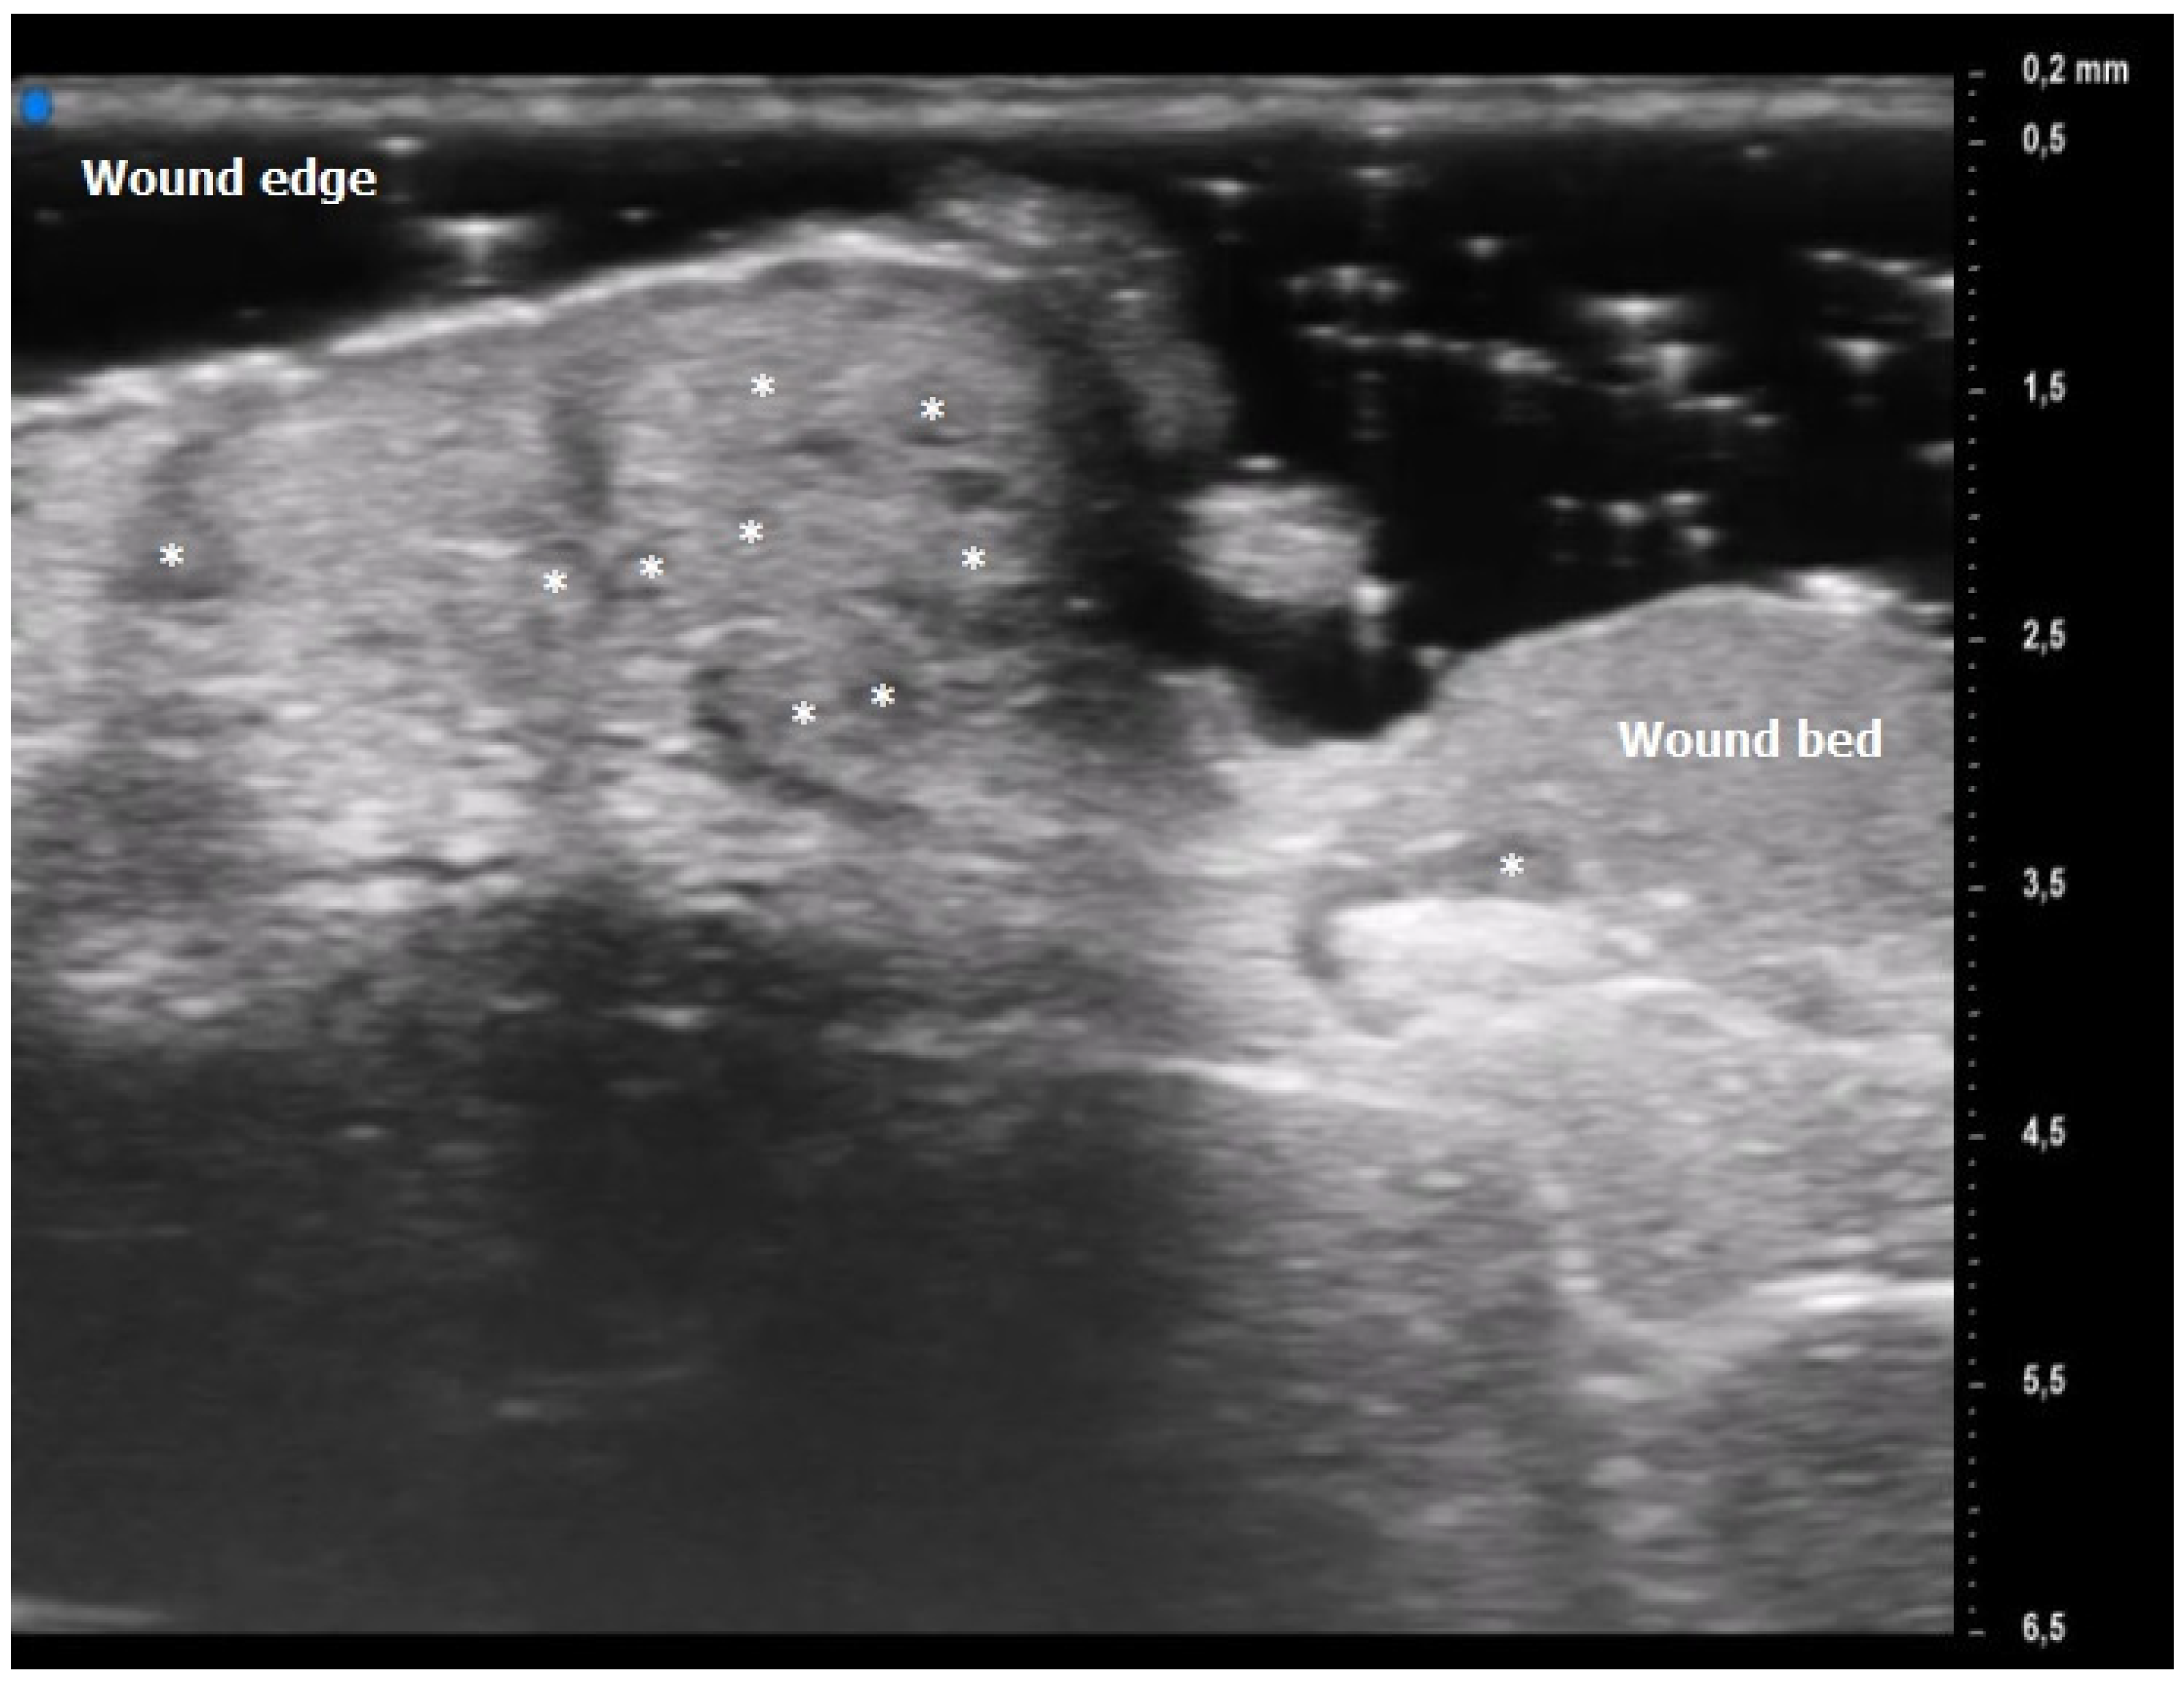

Oval hyperechoic structures were identified in the reticular and papillary dermis during the initial T0 UHFUS examination. These structures were surrounded by a consistent, homogeneous hypoechoic background. Notably, this peculiar arrangement was observed in both the pustular and ulcerative phenotypes, indicating a common underlying feature.

As the examination progressed towards the inflamed edge, these oval structures exhibited a noticeable increase in prevalence, reinforcing their association with the inflammatory process.

A statistically significant decrease in the presence of these hyperechoic oval structures was observed during the subsequent T1 UHFUS examination. This reduction in prevalence (p value < 0.05) underscores the dynamic nature of these structures and their potential correlation with the progression of the inflammatory response (Figure 2).

The results obtained by our investigation revealed some UHFUS differences between the inflammatory and non-inflammatory phases. At T0, oval hyperechoic structures, that statistically significantly decreased in T1, were identified in the papillary and reticular dermis (p-value < 0.05) (Figure 4 and Figure 5).

These US findings spared the epidermis and were well demarcated from the surrounding dermis, thus suggesting a hypothesis of “dermal destruction” that we called “tsunami sign” because of the presence of a US image resembling a wave breaking towards the center of the lesion (Figure 6). In T0, hyperechoic oval structures were mainly located at the level of the lesion edges, near V-shaped and U-shaped blood vessels, where the inflammatory response presented a higher activity. Particularly, in T0 an increased expression of U-shaped vessels compared to V-shaped vessels was detectable. In contrast, T1 was characterized by a more uniform vascularization with a significant reduction in U-shaped vessels (p-value < 0.05). These UHFUS findings could be explained by the increased dermal oedema in T0, which resulted in surrounding connective tissue compression and morphological blood vessels changes.

Figure 2. Pyoderma Gangrenosum (PG) Ultra-High Frequency UltraSound (UHFUS) features during the inflammatory phase (T0): oval hyperechoic structures (*) surrounded by hypoechoic borders predominantly located at the ulcer edge.